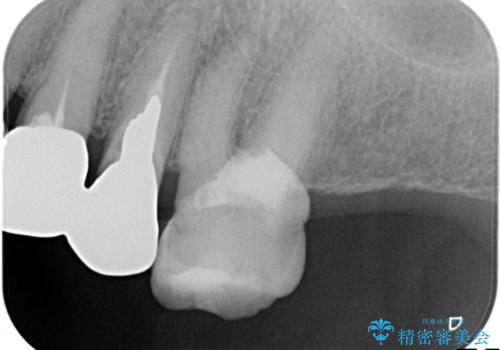

- 奥歯がなくて咬めないのと、全体的に見た目をよくしたいとのことで来院されました。

下顎の両側の奥歯が欠損しており、入れ歯をお持ちでしたが、うまく咬めずにほとんど使用していない状態でした。

上顎は全体的にクラウンの入れ替えと、下顎はインプラントの提案もしましたが、希望されなかったのでノンクラスプデンチャーの製作をする治療計画としました。

奥歯が欠損しており、上下の前歯が強く咬合する可能性があったので、上顎前歯の裏側は金属のものにしました。